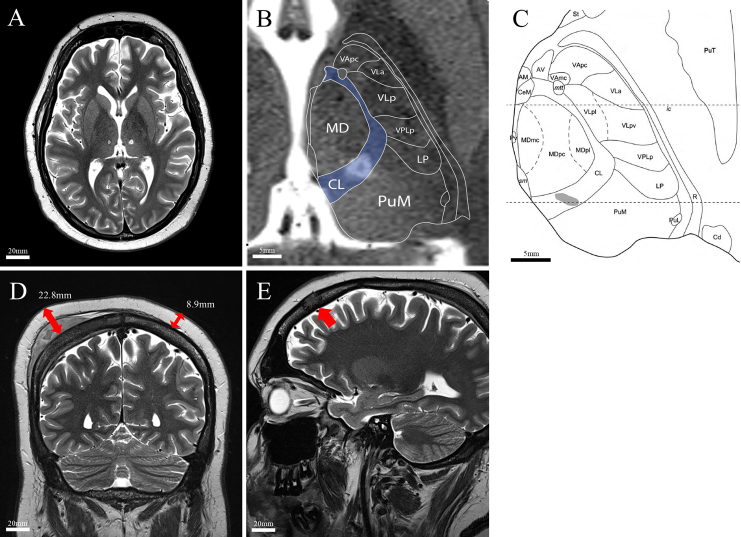

Background: Neuropathic cancer pain (NCP) is a debilitating condition that is often refractory to conventional medical management. MRI-guided focused ultrasound (MRgFUS) central lateral thalamotomy (CLT) is an incisionless neurosurgical option for neuropathic pain palliation, but its use in pediatric patients and those with cranial metastases, a relative contraindication to MRgFUS, remains largely unexamined.

Observations: A 16-year-old male with metastatic rhabdomyosarcoma (RMS) with numerous cranial metastases experienced severe, diffuse, refractory NCP. The patient underwent bilateral CLT with MRgFUS. After the procedure, the patient experienced complete and durable resolution of his neuropathic pain. He only reported occasional somatic pain at sites of visible tumor growth. His pain remained well controlled until his death 1.5 months later due to disease progression.

Lessons: MRgFUS CLT appears to be a feasible and efficacious option for adolescent cancer patients with atypical cranial anatomy due to metastatic disease. This case highlights the potential for durable pain control in refractory NCP and suggests MRgFUS as a valuable palliative tool, warranting further investigation in pediatric patients and unique anatomical scenarios. https://thejns.org/doi/10.3171/CASE25221.